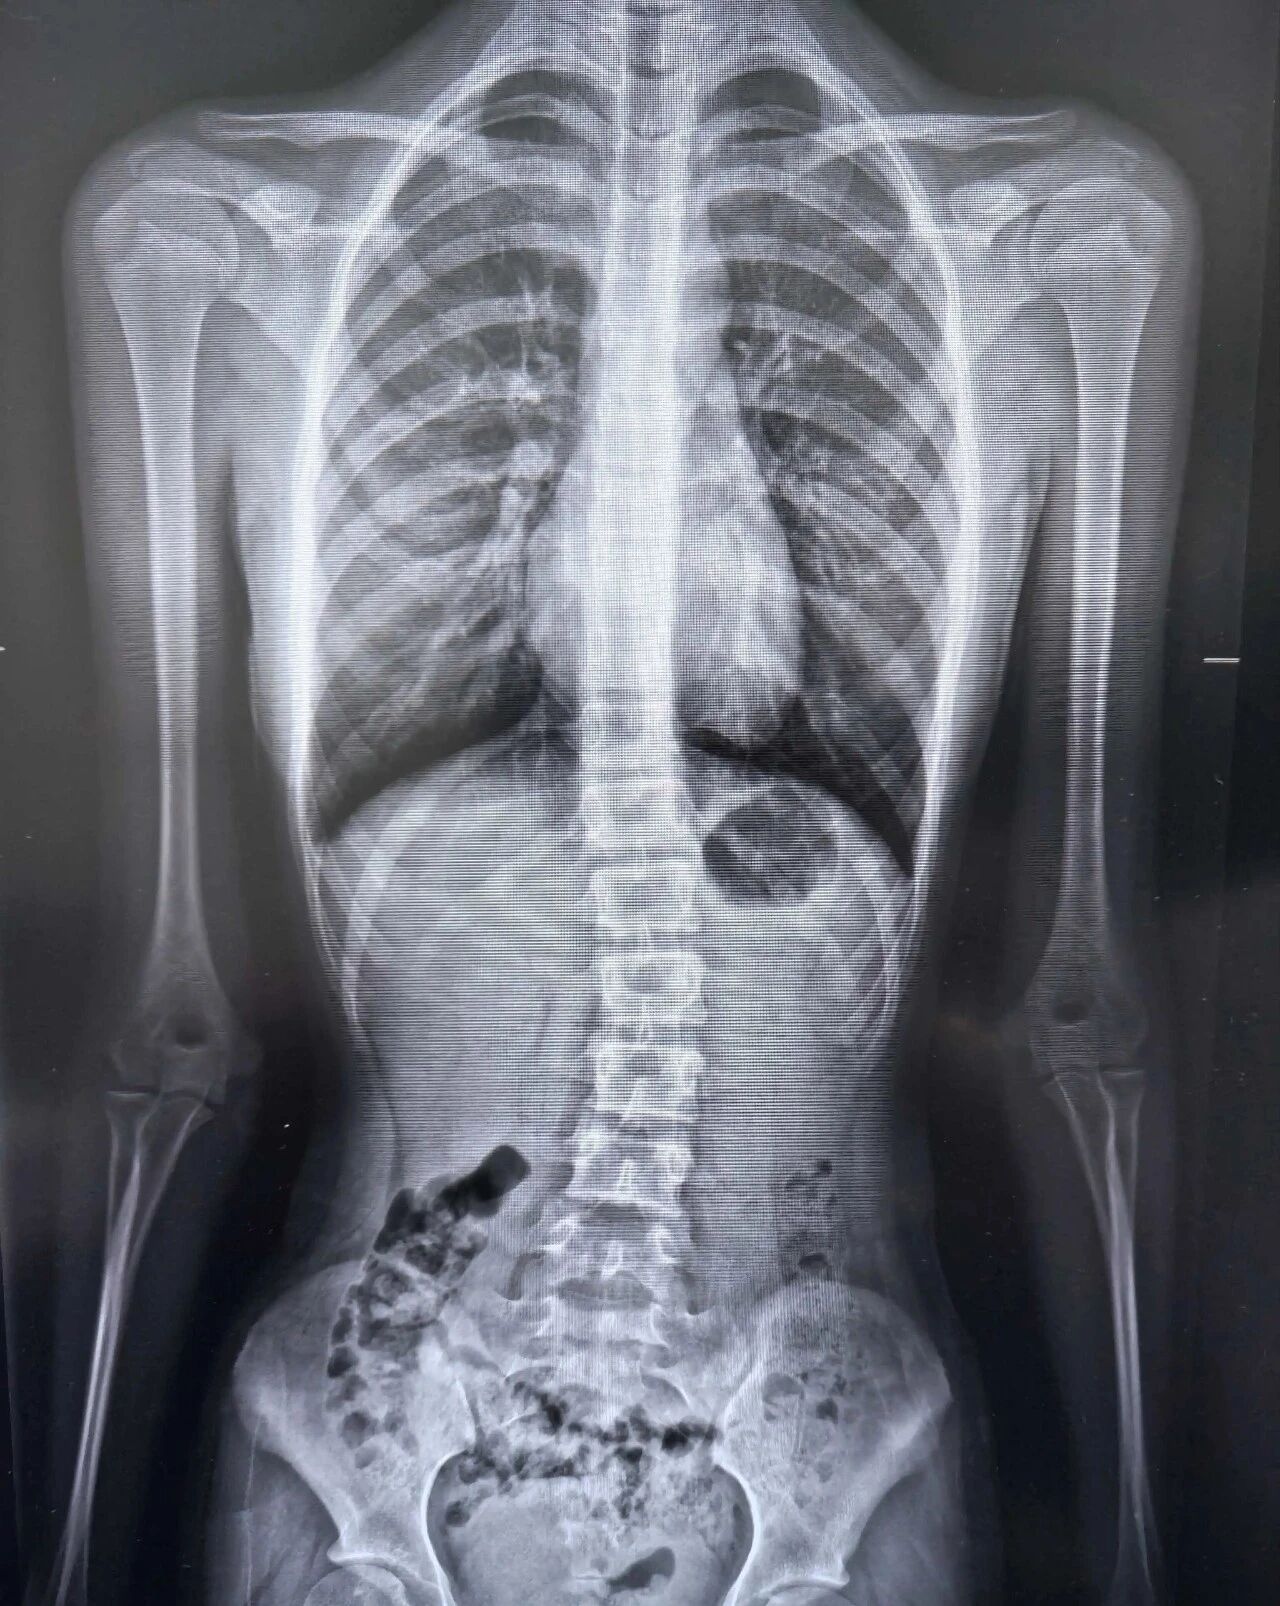

下面让我们一起来详细了解一下“西门子Ysio Max”探测器吧!一、核心技术优势Ysio Max探测器通过创新设计与智能功能,在临床应用中展现出显著优势:1.创新探测器设计:针对性设计的探测器,提升灵活性与适用性。静态MAX(17×17英寸通用探测器):覆盖常规检查场景,适用性广。2.智能操作优化功能:MAXalign实时角度显示:实时显示探测器与X射线管角度,快速对准减少辐射暴露,提升检查效率;探测器触摸显示屏:集成关键信息显示与参数调整功能,简化操作流程,降低人为误差。3.长骨全景成像技术:支持高精度长骨拼接成像(拼接准确、速度快),适用于测定负重骨骼生物力线、脊柱侧凸角等复杂临床场景。

二、成像质量表现Ysio Max探测器通过技术优化,在常规及复杂场景中均能提供优质影像:1.高分辨率与细节捕捉:配备新一代九百万像素平板探测器,显著提升图像分辨率,满足高精度诊断需求。2.技术优化提升质量:钻石窗技术:减少干扰,增强影像对比度与清晰度;碘化铯材料探测器:高效转换X射线信号,提升成像准确性;16比特灰阶:呈现更丰富灰度层次,辅助精准识别病变细节。3.复杂场景稳定性:长骨全景成像技术在骨骼生物力线测定等场景中表现稳定,图像清晰可靠,为手术提供关键依据。